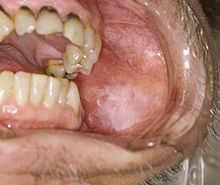

Leukoplakia

The white lesion is an example of leukoplakia.

Leukoplakia is a clinical term used to describe patches of keratosis . It is visible as adherent white patches on the mucous membranes of the oral cavity, including the tongue, but also other areas of the gastro-intestinal tract, urinary tract and the genitals. The clinical appearance is highly variable. Leukoplakia is not a specific disease entity, but is diagnosis of exclusion. It must be distinguished from diseases that may cause similar white lesions, such as candidiasis or lichen planus.